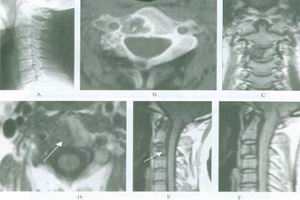

2.CT及MRI檢查CT檢查費用雖較X線照片高,但其密度分辨高於X線、對病骨內的囊變、破壞、鈣化和骨化顯示較X平片敏感準確。CT橫斷面克服了常規X平片前後重疊的缺點,可用於頭顱、脊柱和骨盆等重疊較多的部位。MRI對MAS的病理顯示無疑較常規X線或CT更敏感,能顯示大部分在X線平片或CT片上不能顯示的病灶(如壞死、液化、出血),纖維或纖維骨樣組織病灶在T1加權像和T2加權像均呈低信號。骨幹結構不良在病變的不同階段可有不同的病理改變。如病灶內的壞死液化在T1加權像上呈低信號,在T2加權像上呈高信號。如壞死組織合併出血,T1加權像上呈高信號。病灶內的鈣化和周緣的硬化在T1加權像和T2加權像上呈明顯的低信號。此外,少數病灶邊緣在T1和T2加權像上呈薄帶狀環狀高信號,其病理機制不清。某些病灶在T1加權像上呈不均勻的中低信號,而在T2加權像上則平片所見的“絲瓜筋”樣纖維結構不良。而液化的病灶在T1加僅像上為中低信號,在T2加權像上為均勻高信號。